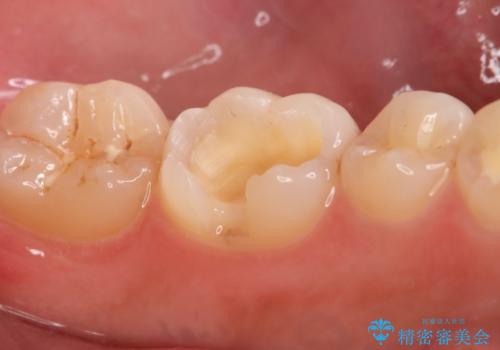

- 左下6番の治療のやり直しを希望し来院された患者様です。

保険の材料が劣化し段差や隙間ができてしまっている状態です。

自費の治療を希望されたため切削量・形態を考慮し、セラミックインレーでの治療を計画しました。